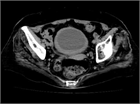

1. 出血性膀胱炎とは、膀胱粘膜の炎症により肉眼的血尿を認める疾患である。肉眼的血尿に加え、頻尿・排尿時痛や残尿感などの症状を伴うことがある。

1. 原因として、ウイルス、細菌、薬剤、放射線治療後などが挙げられ、小児ではアデノウイルスによる頻度が高い。薬剤性では、抗がん薬(シクロホスファミド、イホスファミド)、免疫抑制剤、抗アレルギー薬などが有名であるが、抗生物質、漢方薬(小柴胡湯出血性膀胱炎など)などでも報告がある[1]

1. 治療は原因の除去および治療である。原因の除去により症状が改善することが多いが、改善しない場合は点滴による利尿、血尿が強く持続する場合は持続膀胱洗浄を行う。また放射線治療による場合は、高圧酸素療法が有効である(推奨度2)[1]